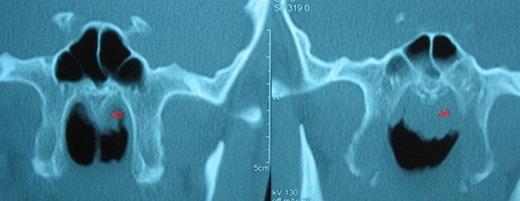

A computed tomography (CT) was performed and a left sided mass in the inferior meatus which has demonstrated central calcification was reported (Figure 1). Mild mucosal hypertrophy was present in the left ethmoid and maxillary sinuses, accompanied with ipsilateral asymmetric adenoid hypertrophy (Figure 2).

Rinolith is seen on the left nasal cavity. (r: rinolith, O: orbit, M: Maxillary sinus)